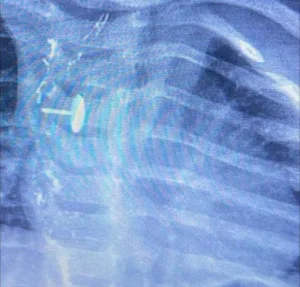

الطفلة، البالغة من العمر سنة وسبعة أشهر، كانت تعاني منذ شهور من صعوبة شديدة في البلع، مصحوبة بآلام متكررة في منطقة الصدر، مما أثار قلق أسرتها التي لجأت إلى أكثر من جهة طبية بحثًا عن تفسير لحالتها، حتى تم تحويلها إلى مستشفى بنها التخصصي، حيث كشفت الأشعة والفحوصات الدقيقة عن المفاجأة الصادمة: وجود دبوس معدني مغروس داخل جدار المريء.

وبحسب بيان المستشفى، جرى تجهيز الطفلة فورًا لإجراء عملية جراحية معقدة تطلبت تنسيقًا عالي المستوى بين عدة تخصصات، إذ استعان الفريق الطبي بمنظار الجهاز الهضمي وجهاز الأشعة المتطور “سي آرم” ومنظار القصبة الهوائية لتحديد موضع الدبوس بدقة، قبل أن ينجح الأطباء في استخراجه دون أي مضاعفات، وسط متابعة دقيقة لحالة الطفلة حتى استقرت تمامًا وعادت إلى حالتها الطبيعية.